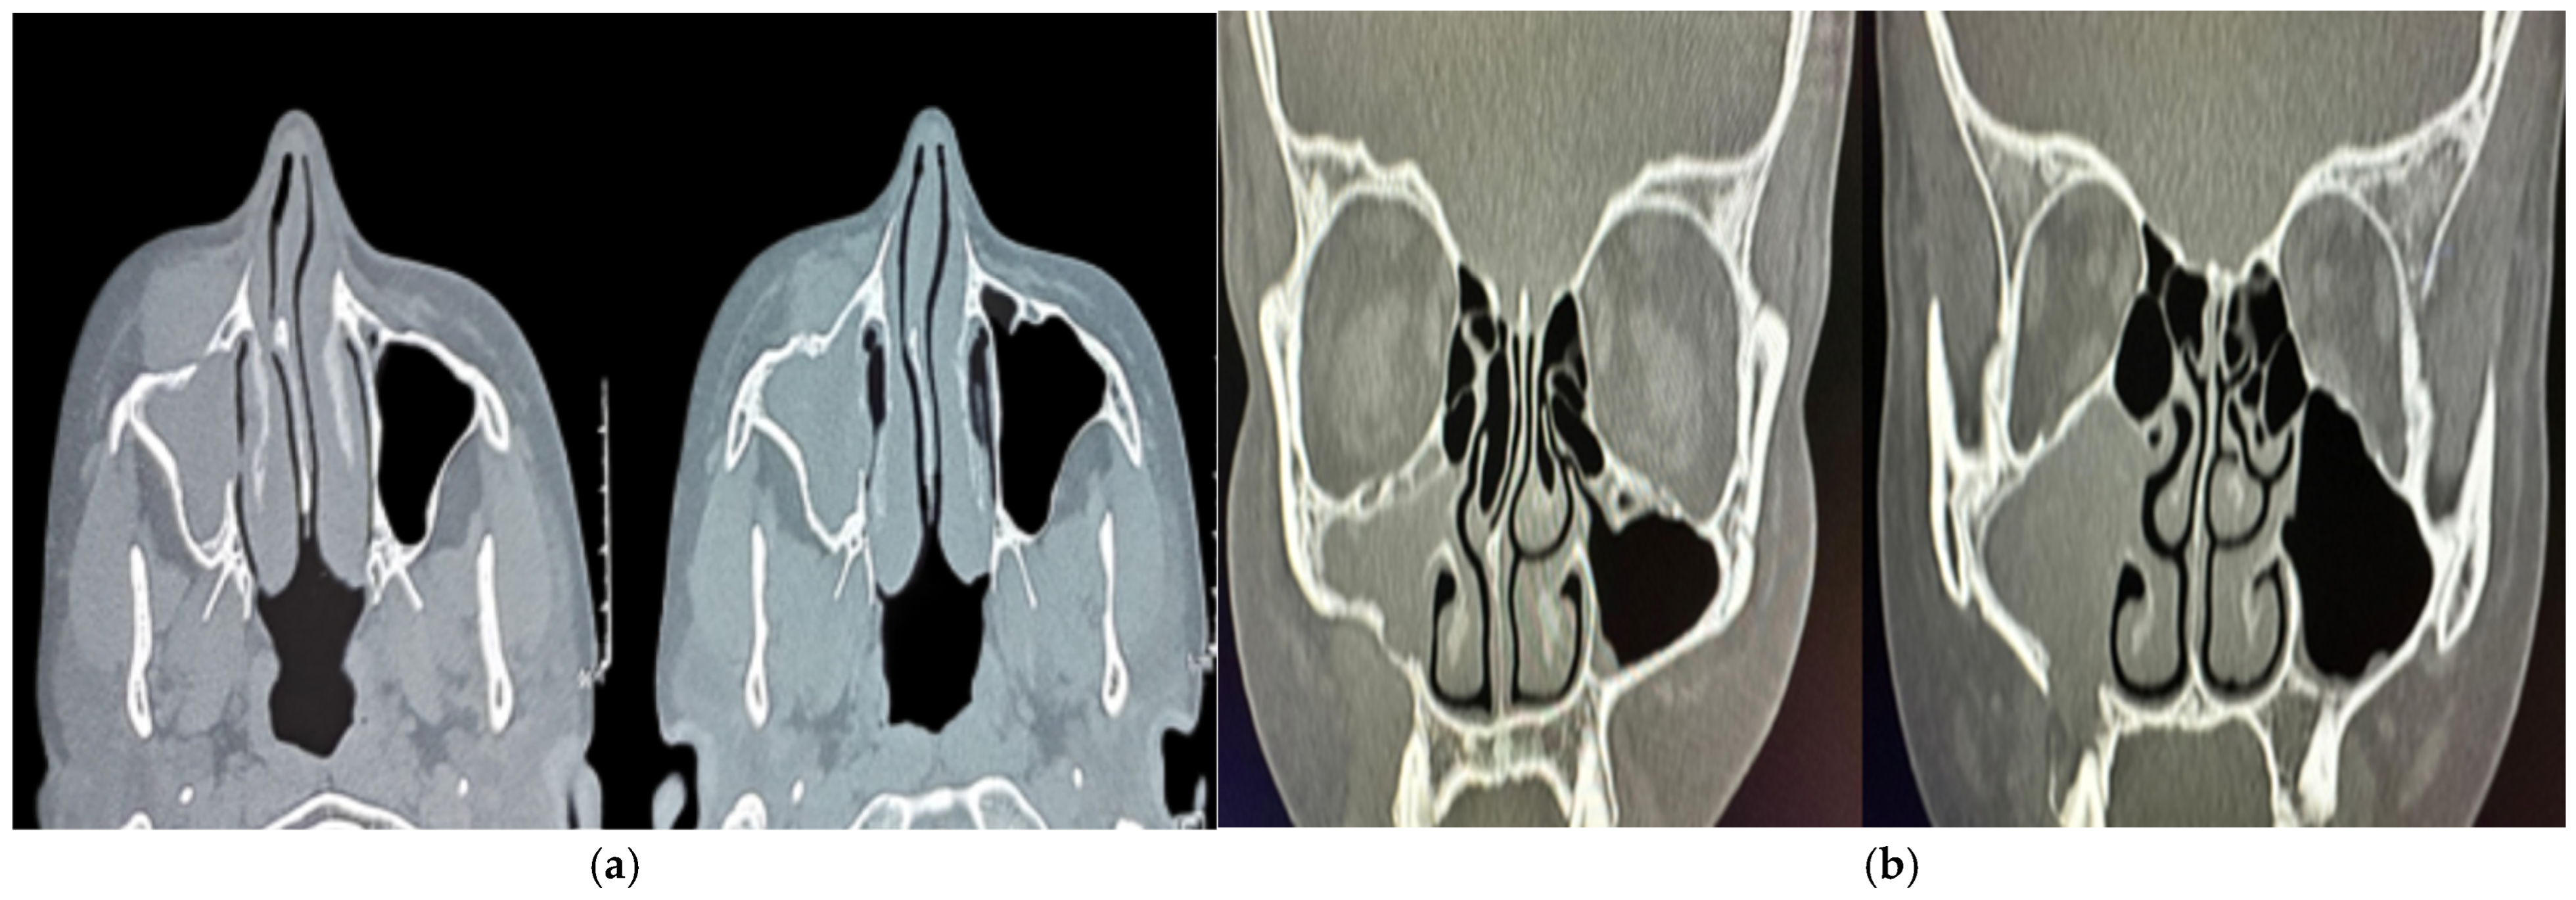

2. Case Presentation